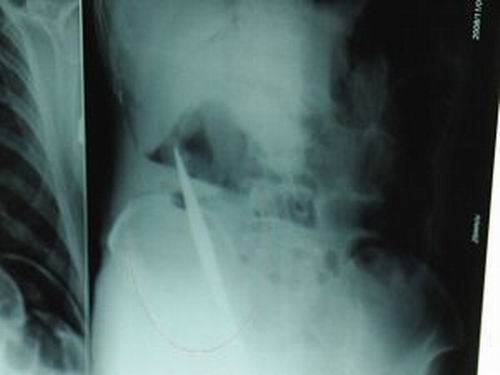

X光片上,尖刀清晰可見。

從男子體內(nèi)取出的尖刀足足有19厘米長。

江蘇銅山一58歲男子因服毒被送到醫(yī)院搶救,可醫(yī)生采取搶救措施后卻發(fā)現(xiàn)效果不佳。后來經(jīng)細致檢查,醫(yī)生有了個驚人的發(fā)現(xiàn),該男子的體內(nèi)竟然有一把尖刀,醫(yī)生通過手術將位于其腹部右側橫結腸下緣的尖刀取了出來。這把尖刀足足有19厘米長!據(jù)醫(yī)生推測,這把刀應該是從肛門推進體內(nèi)的,不知男子為何想以如此殘酷的方式結束自己生命。由于搶救及時,該男子已暫時脫離危險。

昨天(11月6日)上午,記者在徐州礦務集團總醫(yī)院重癥監(jiān)護室見到了這名男子,目前他雖然已經(jīng)恢復了意識,但還不能開口說話,需要呼吸機輔助呼吸。據(jù)醫(yī)生介紹,4日中午12時左右,這名男子因服毒輕生被緊急送到醫(yī)院進行搶救,之前,這名男子已經(jīng)在當?shù)剜l(xiāng)鎮(zhèn)醫(yī)院進行了近20小時的治療,但效果不佳。“病人被轉院到礦總院時已神志不清,血壓極低,處于休克狀態(tài)!本茸o人員給男子洗胃、初步處理以后,發(fā)現(xiàn)男子呼吸急促,于是趕緊給他拍片檢查。結果讓所有的醫(yī)生大吃一驚,竟有一把尖狀異物橫在該男子腹腔內(nèi)!當天下午5時30分,輕生男子被推上了手術臺。經(jīng)過40多分鐘的手術,該男子腹腔被打開,手術醫(yī)生發(fā)現(xiàn),男子體內(nèi)的金屬狀異物竟然是一把長19厘米的尖刀!

醫(yī)生告訴記者,手術后,醫(yī)生在病人身上并未發(fā)現(xiàn)刀痕,最后,經(jīng)過檢查發(fā)現(xiàn),在該男子直腸處找到穿孔。醫(yī)生從醫(yī)學角度分析后認為,這把尖刀應該是從肛門插入直腸的。